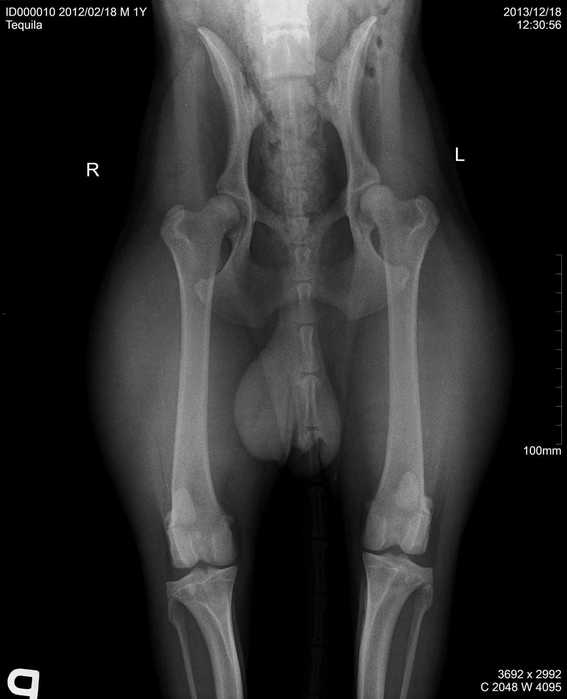

Úvod > Galerie > RTG snímky